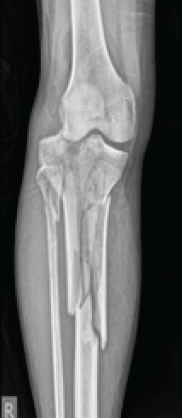

Retrograde Intramedullary Nailing Versus Locked Plating for Periprosthetic Distal Femur Fractures: A Propensity-matched Cohort from TriNetX

Aamir Shahzad , Haji Bahar Ali , Hasnain Chohan , Fouad Kaddour-Hocine , Amna Shoaib , Ismail Pandor

………………………………p.317-328